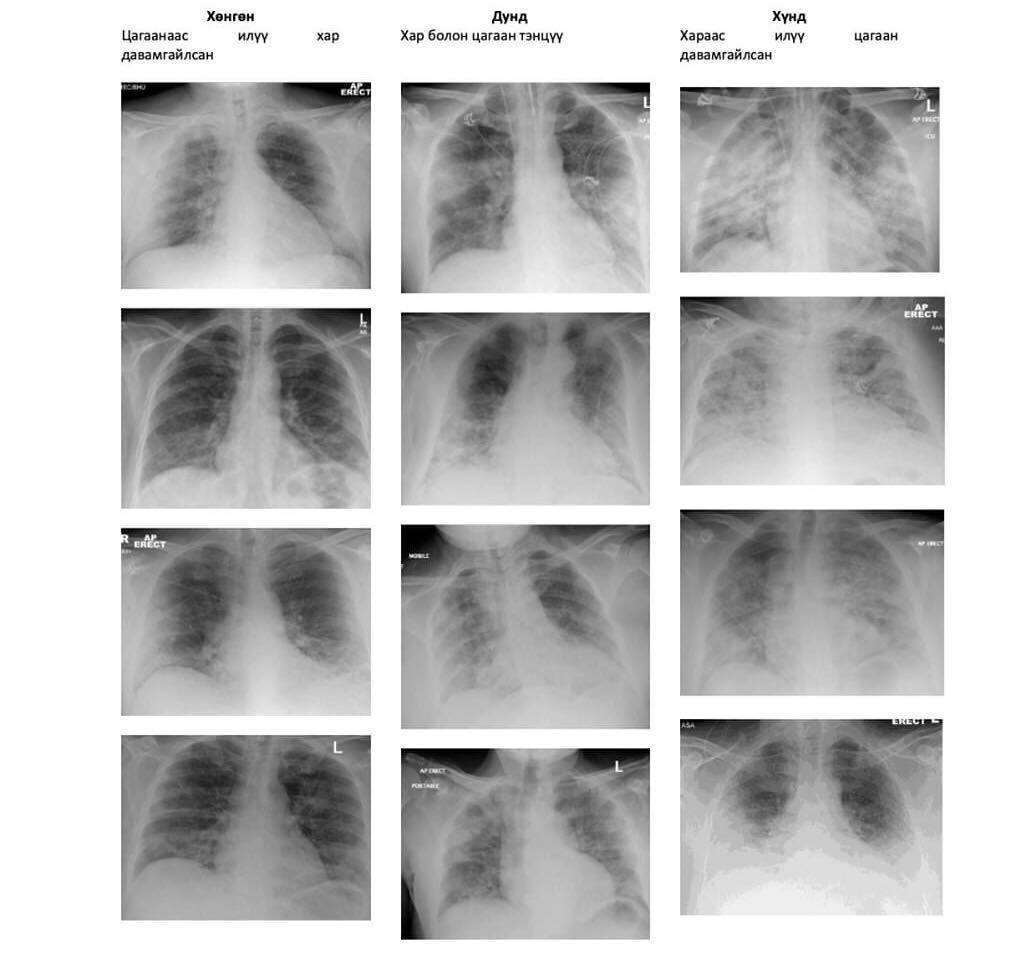

Дараах зурагт коронавирусээр хөнгөн, хүндэвтэр, хүндээр өвчилсөн иргэдийн уушгины рентген зурагны харьцуулсан харьцуулалтыг хүргэж байна.

-Коронавирус хүний уушгийг хамгийн их гэмтээдэг. Тэр тусмаа хүний уушгины хамгийн арын хэсэг буюу захын байрлалд ихээхэн нэвчдэс үүсгэж байгаа. Ковидоор хүнд өвчилсөн хүнд  хатгаа үүссэн байдаг.  Хатгааны үлдэгдэл нь сорвижоод хатуурсан юм шиг зураглалтай харагдана. Хэрэв эмч рентген зураг авахуулах шаардлагатай гэж оношилсон бол нэг жилийн хугацаанд хэдэн ч удаа харуулж болно.